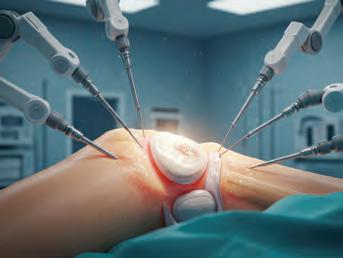

A new precision surgery is now publicly available on the Coast –a first in the state – sparing as much healthy tissue as possible.

Sunshine Coast Health patients diagnosed with skin cancers on or near their eyelids can now access a new type of precision surgery that reduces the risk of recurrence while preserving as much of the eyelid as possible.

Known as the ‘skin cancer capital of the world’, the Sunshine Coast is now home to Queensland’s first publicly funded Mohs surgery clinic and Australia’s first dedicated Mohs and oculoplastic unit.

Mohs surgery is a precise, staged technique for removing skin cancers. It involves thin layers of tissue being removed and examined in real time,

continuing until no cancer cells remain.

Sunshine Coast Health ophthalmologist specialising in ocular plastic surgery Dr Ebony Smith says this ensures complete tumour removal, while sparing as much healthy tissue as possible.

“When you normally cut out a skin cancer, you have to take out a safety margin around that skin cancer to make sure you’ve got the whole thing. But Mohs surgery means you can cut right near the skin cancer, leaving the healthy tissue behind,”

Dr Smith says.

“And you examine it under the microscope in a different way so you can see that you have the whole cancer.”

“To preserve each millimetre around the eye means you’re keeping more of your native eyelid,” Dr Read says.

“We can also try to preserve really important structures like the lacrimal apparatus which drains the tears, which has a really functional effect, as well as being a really cosmetically sensitive area.”

The real-time testing in this new approach allows patients to have the whole process done in one day – rather than going home to wait for results and then returning for further surgery.

“So, if you think about our first patient, who is a nurse from Gympie, that’s her travelling all the way to Gympie two, three times more than what she does if we just get it all done today,” Dr Smith says.

While eyelid skin cancers aren’t as common as in other parts of the body, the team is expecting many patients to benefit from this surgery.

“Most of the skin cancers we see around the eye are about cumulative sun damage and, living somewhere like Southeast Queensland, there’s obviously a lot of sun and it’s also an area where it’s very difficult to apply sunscreen,” Dr Read says.

Caloundra Health Service director of nursing Amy Carey says the surgical team is

proud to offer this unique collaborative service for locals.

“We want to say a really big ‘thank you’ to the Caloundra Hospital Auxiliary for being huge supporters of this service and providing us the new equipment for this surgery,” she says.

Lyn Carr is thrilled to have been one of the first patients to be treated with Mohs at Caloundra Health Service. She was surprised when what she originally thought was an ulcer on her lower eyelid turned out to be a basal cell carcinoma (BCC).

“I’ve been lucky with my eyes all through my life,” Lyn says.

In fact, she’s always particularly loved her blue eyes, since she first met her husband at 17.

“When he said, ‘Can I see you again?’, I think one of the first things he said to me was ‘I loved your eyes’,” she remembers.

Lyn was excited to be able to access Mohs surgery and relieved to know only the minimal amount of tissue would be removed, while also reducing the chance of any cancer coming back.

“I just feel full of confidence. I really do,” Lyn says.